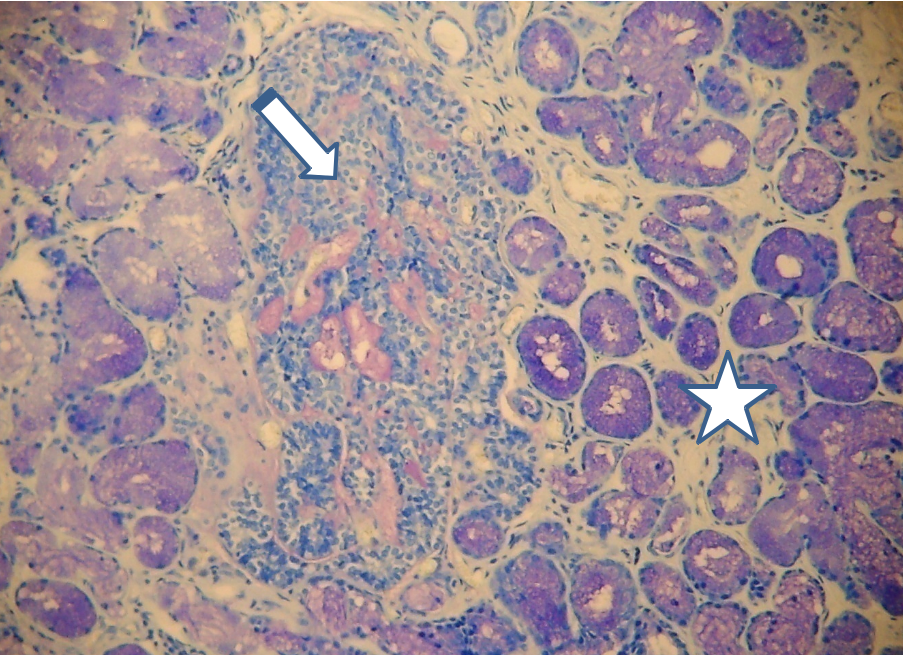

Adenoma canalicular (flecha). Glándulas labiales (estrella) Azul de toluidina

Adenoma canalicular (flecha). Glándulas labiales (estrella). PAS/H